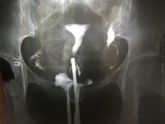

Девочки сегодня было гсг , результат , левая труба сактосальпинкс , правая частично проходимая , беременели вы с таким диагнозом, как скоро, и вообще как лечили ? ?????